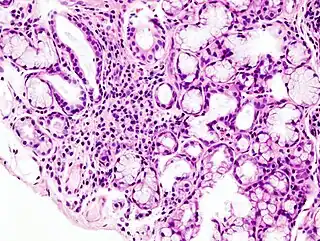

![]() Imagen histopatológica de infiltración en la glándula salivar menor asociada con el síndrome de Sjögren. Biopsia labial. H & E stain. | ||